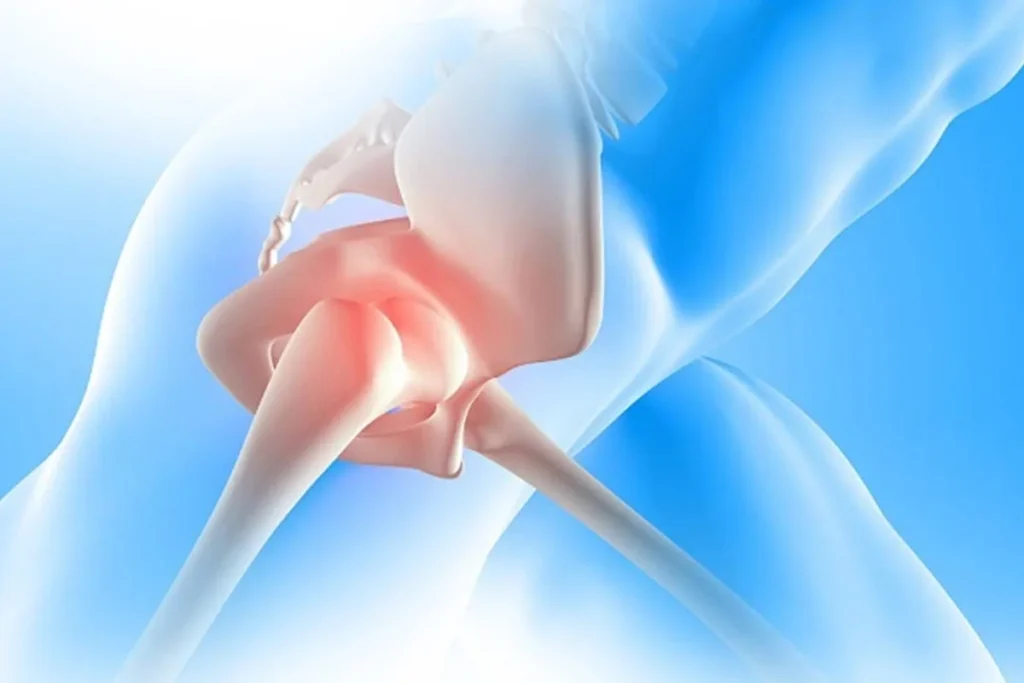

The procedure is meant to address that. The damaged part of the joint is replaced with an artificial one so that movement becomes smoother and less painful.

The surgery itself remains the same whether it is done in winter or peak summer.